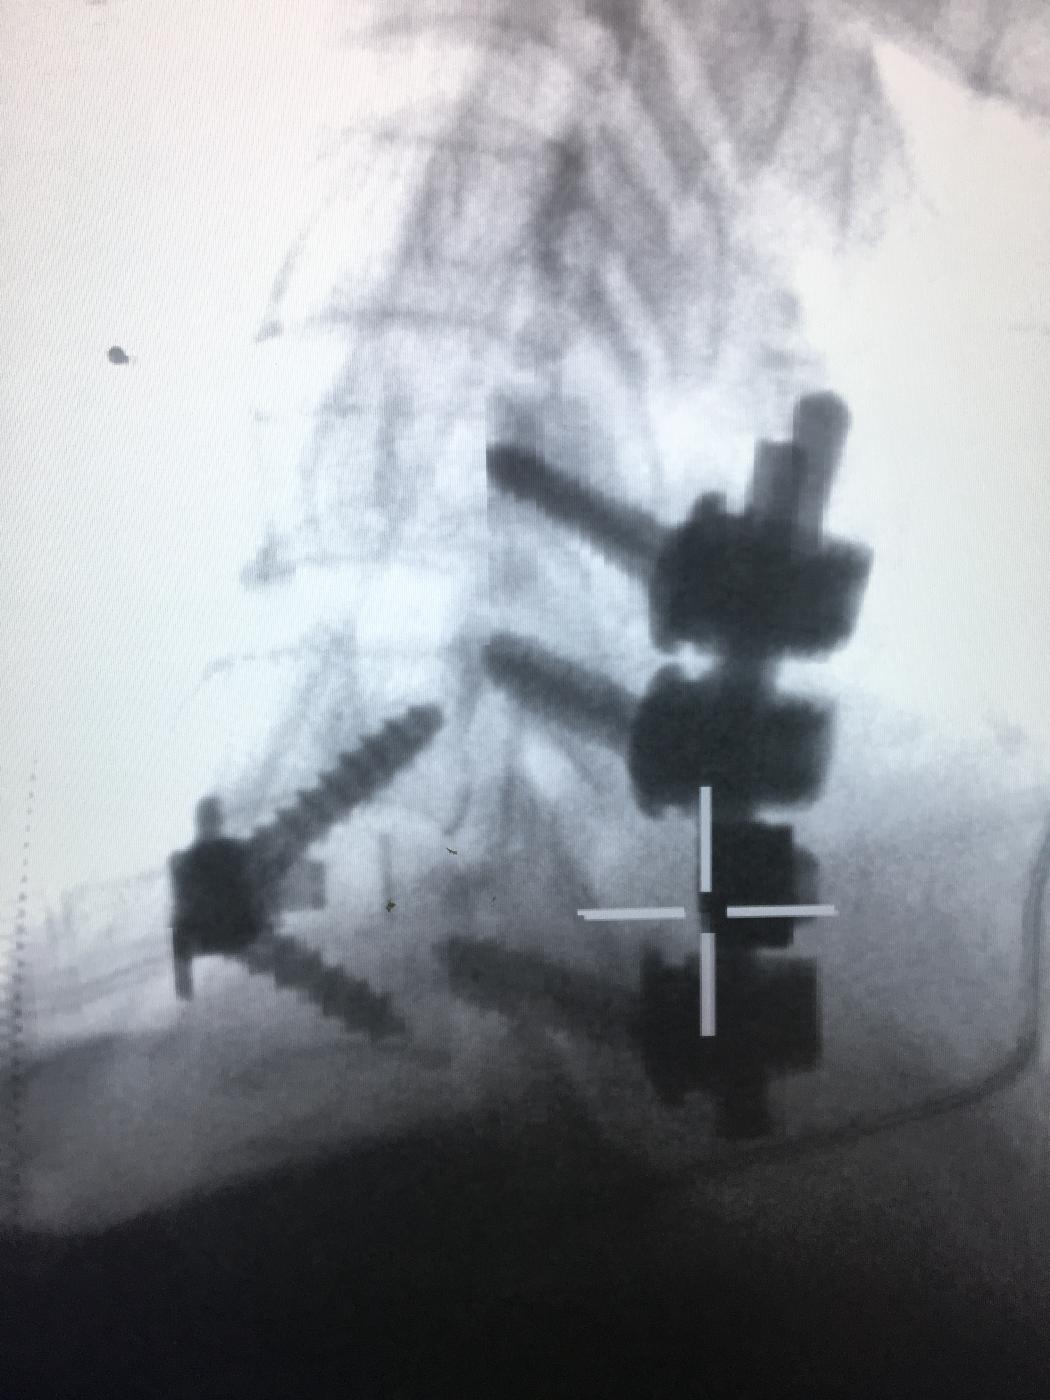

颈椎前后路减压固定融合术 发布时间:2018/1/22 11:21:00       浏览次数:5970次

(3)稳定脊柱:一般于复位后进行内固定,并酌情予以融合。内固定的方法有后固定及前固定。后固定中主要有短节段内固定Dick、Steffee、RF、AF等椎弓根螺丝固定。Luque、Harrington杆及Roy-Camille等较长段固定,已少用于脊柱骨折脱位。前固定有颈椎前钢板胸腰椎Z钢板等、饶书诚固定钉。各有不同适应证。

(4)脊髓减压:骨折脱位、椎体骨折、后突及椎间盘突出都压迫脊髓前方,因此,多需做侧前方减压或前减压,对此种情况,行椎板切除减压多不奏效,椎板骨折下陷压迫脊髓,需行椎板切除减压。只有充分减压,才为脊髓恢复提供条件。